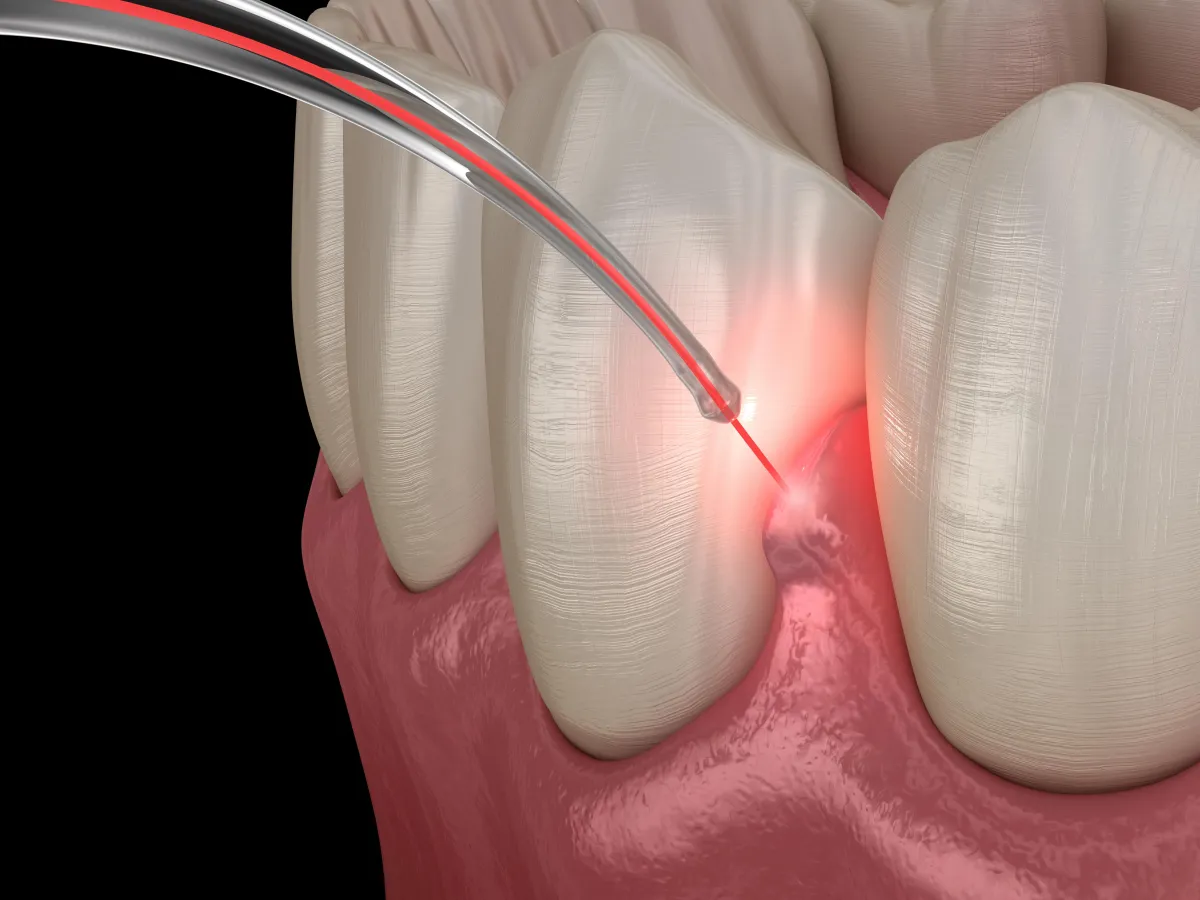

Transforming Implant Dentistry with BLAST

Unlock Gentler Implant Placement with PrecisionArch™ and BLAST

At Chippewa Creek Dental, we’re committed to top-quality dental care using advanced technology focused on your comfort.

That includes laser dentistry and the BLAST Protocol (Biostimulation-Lase-Activation-Stimulation-Technique) a powerful combination for faster healing, better results, and less discomfort.

We use laser technology during implant placement surgery to enhance precision, reduce bleeding, and promote faster healing.

Because lasers target tissue more precisely, they improve surgical outcomes and patient comfort, making the procedure more efficient and less invasive.

Even if you’ve been told you’re not a candidate due to gum disease or bone loss, BLAST may offer a solution.

Removes bacteria and infected tissue

Speeds up healing by activating bone and gums

Boosts stability and appearance with precise placement

Minimizes complications through soft tissue control

Maximizes long-term success with smart timing

Whether you need one implant or a full-mouth restoration, BLAST helps us create durable, beautiful smiles with greater comfort and confidence.